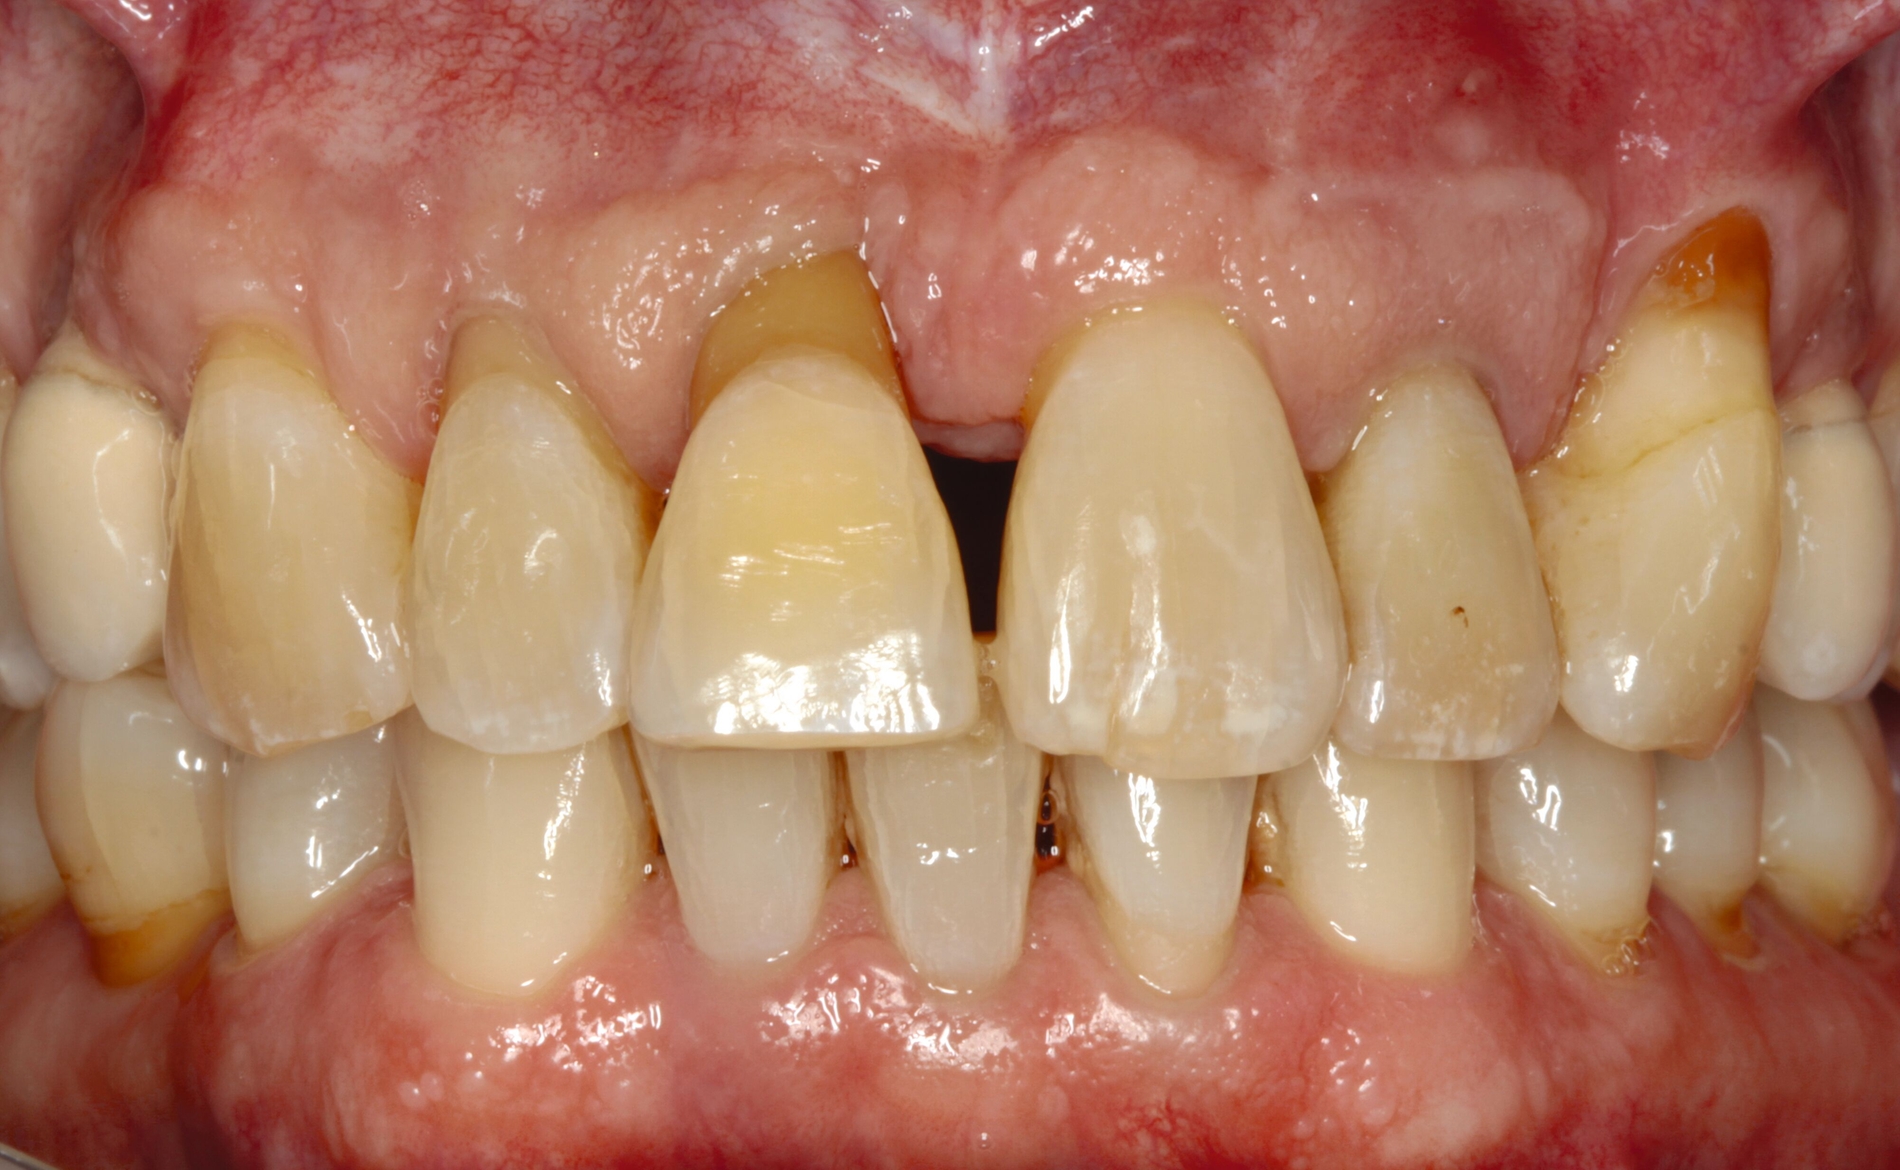

Möglichkeiten zur Therapie des okklusalen Traumas sind das selektive Einschleifen okklusaler Frühkontakte, die Schienung der betroffenen Zähne oder gegebenenfalls auch kieferorthopädische Bewegungen der Zähne sowie eine Kombination der genannten Therapieformen [Fan und Caton, 2018; Dommisch et al., 2022]. Ein Beispiel für eine Schienung bei Vorliegen einer okklusalen Dysfunktion ist in Abbildung 2 dargestellt.